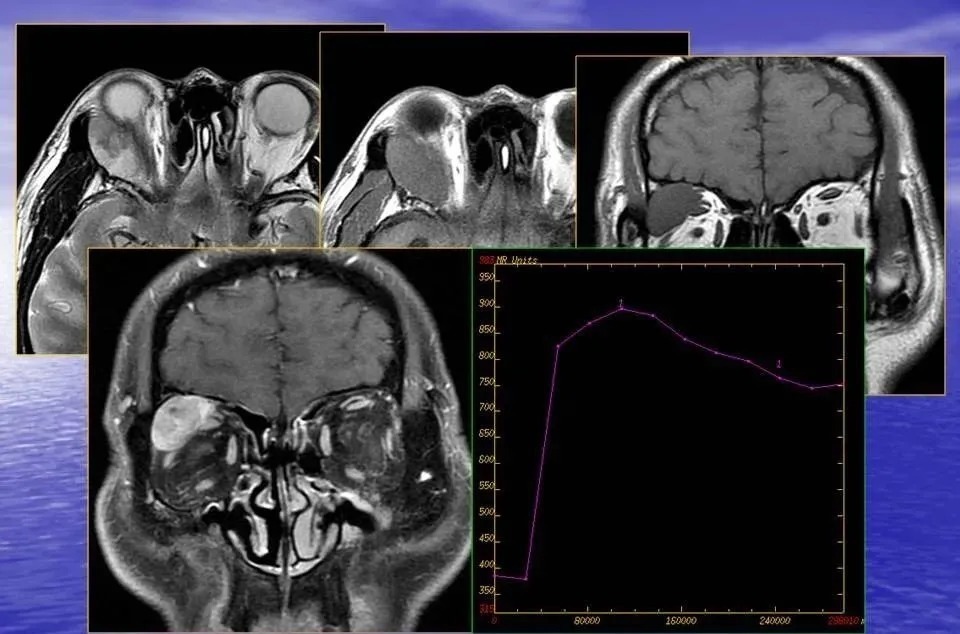

对于肿瘤患者来说,影像诊断是选择治疗方式和疗效评估的关键。通过将形态影像学和功能影像学结合,包括 PET/CT、功能 MRI、功能 CT 等,利用大数据技术挖掘多种影像学的特点并整合分析,来预测临床疗效和患者对治疗手段的应答情况。

影像诊断就是临床医生的另一双眼睛,在普通人眼里的黑白照,在影像科医生的眼里就是诊断疾病的信息入口。